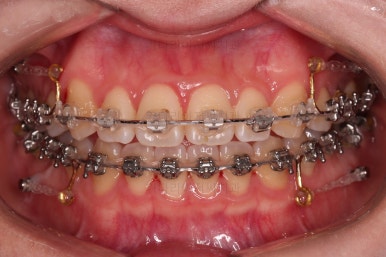

1. 처음 내원 시의 입안의 모습

부산치아교정잘하는곳 키다리아저씨치과에 처음 내원하셨을 당시의 입안 모습입니다.

얼핏 보면 많이 삐뚤어지지는 않은 편인데, 눈에 바로 띄는 앞니가 뻗쳐 있으면서 획 돌아있는데요. 정렬이 필요한 상황이었습니다.

어금니쪽은 많이 삐뚠 편은 아니었으며, 윗니 앞니가 많이 앞으로 뻗쳐 있는 상태였습니다.